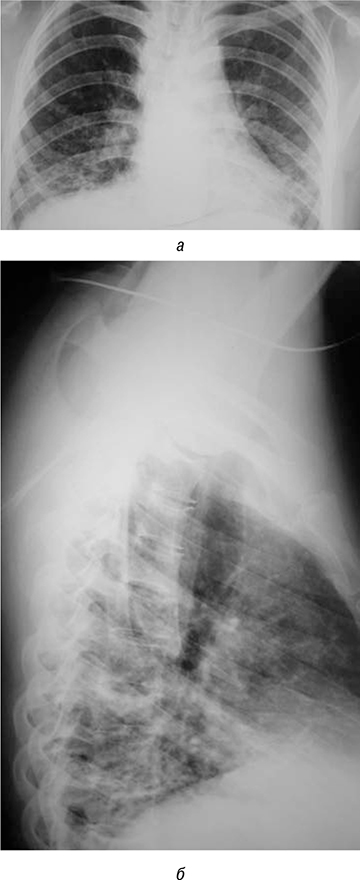

До начала терапии 25.06.2019 г. больной была проведена рентгенограмма органов грудной клетки. Отмечается на фоне обогащения легочного рисунка в средних, нижних легочных полях с обеих сторон наличие участков инфильтрации легочной ткани сливного характера.

01.07.2019 г. была проведена первая инфузия 1000 мг ритуксимаба внутривенно капельно, через 1 сут после введения отмечена отчетливая положительная динамика в виде значительного уменьшения одышки, уменьшения мраморности кожи, улучшение общего самочувствия и намечающаяся положительная рентгенологическая динамика (рис. 5а, б).

Рис. 5. Рентгенограммы органов грудной клетки после первого сеанса терапии ритуксимабом (а, б) (июль 2019 г.)